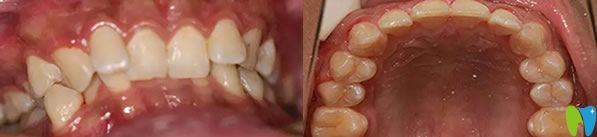

福州登特口腔牙齒矯正前后效果對(duì)比圖:

登特口腔牙齒矯正前后效果對(duì)比圖

這就是我在福州登特口腔做的金屬托槽牙齒矯正14個(gè)月恢復(fù)效果圖,終于解決了我牙齒擁擠不齊的困擾,達(dá)到了預(yù)期的治療效果,恢復(fù)了牙齒的咀嚼功能。而且經(jīng)濟(jì)實(shí)惠整個(gè)診療過(guò)程花了12000元左右,大家覺(jué)得我在福州登特口腔矯正牙齒的價(jià)格貴嗎?